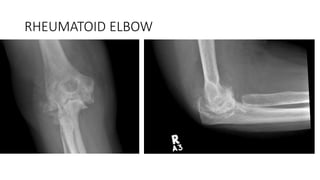

RHEUMATOID ELBOW

• Synovitis- swelling and pain- may develop FFD due to holding in

flexed position

• Annular ligament may rupture- anterior displacement of radial head

due to pull of biceps

• Collateral ligaments may rupture ML instability

• Ulna nerve neuropathy secondary to synovitis and rheumatoid

nodule

• Cartilage and bone destruction- severe cartilage damage causing

instability and bony destruction

Treatment options

• Synovectomy +/- radial head excision

• Arthrodesis / Resection arthroplasty

• Arthroplasty= non constrained, semiconstrained and constrained

Indications :pain, loss of motion and instability

Semiconstrained device has best results

Reliable procedure for advanced RA of elbow